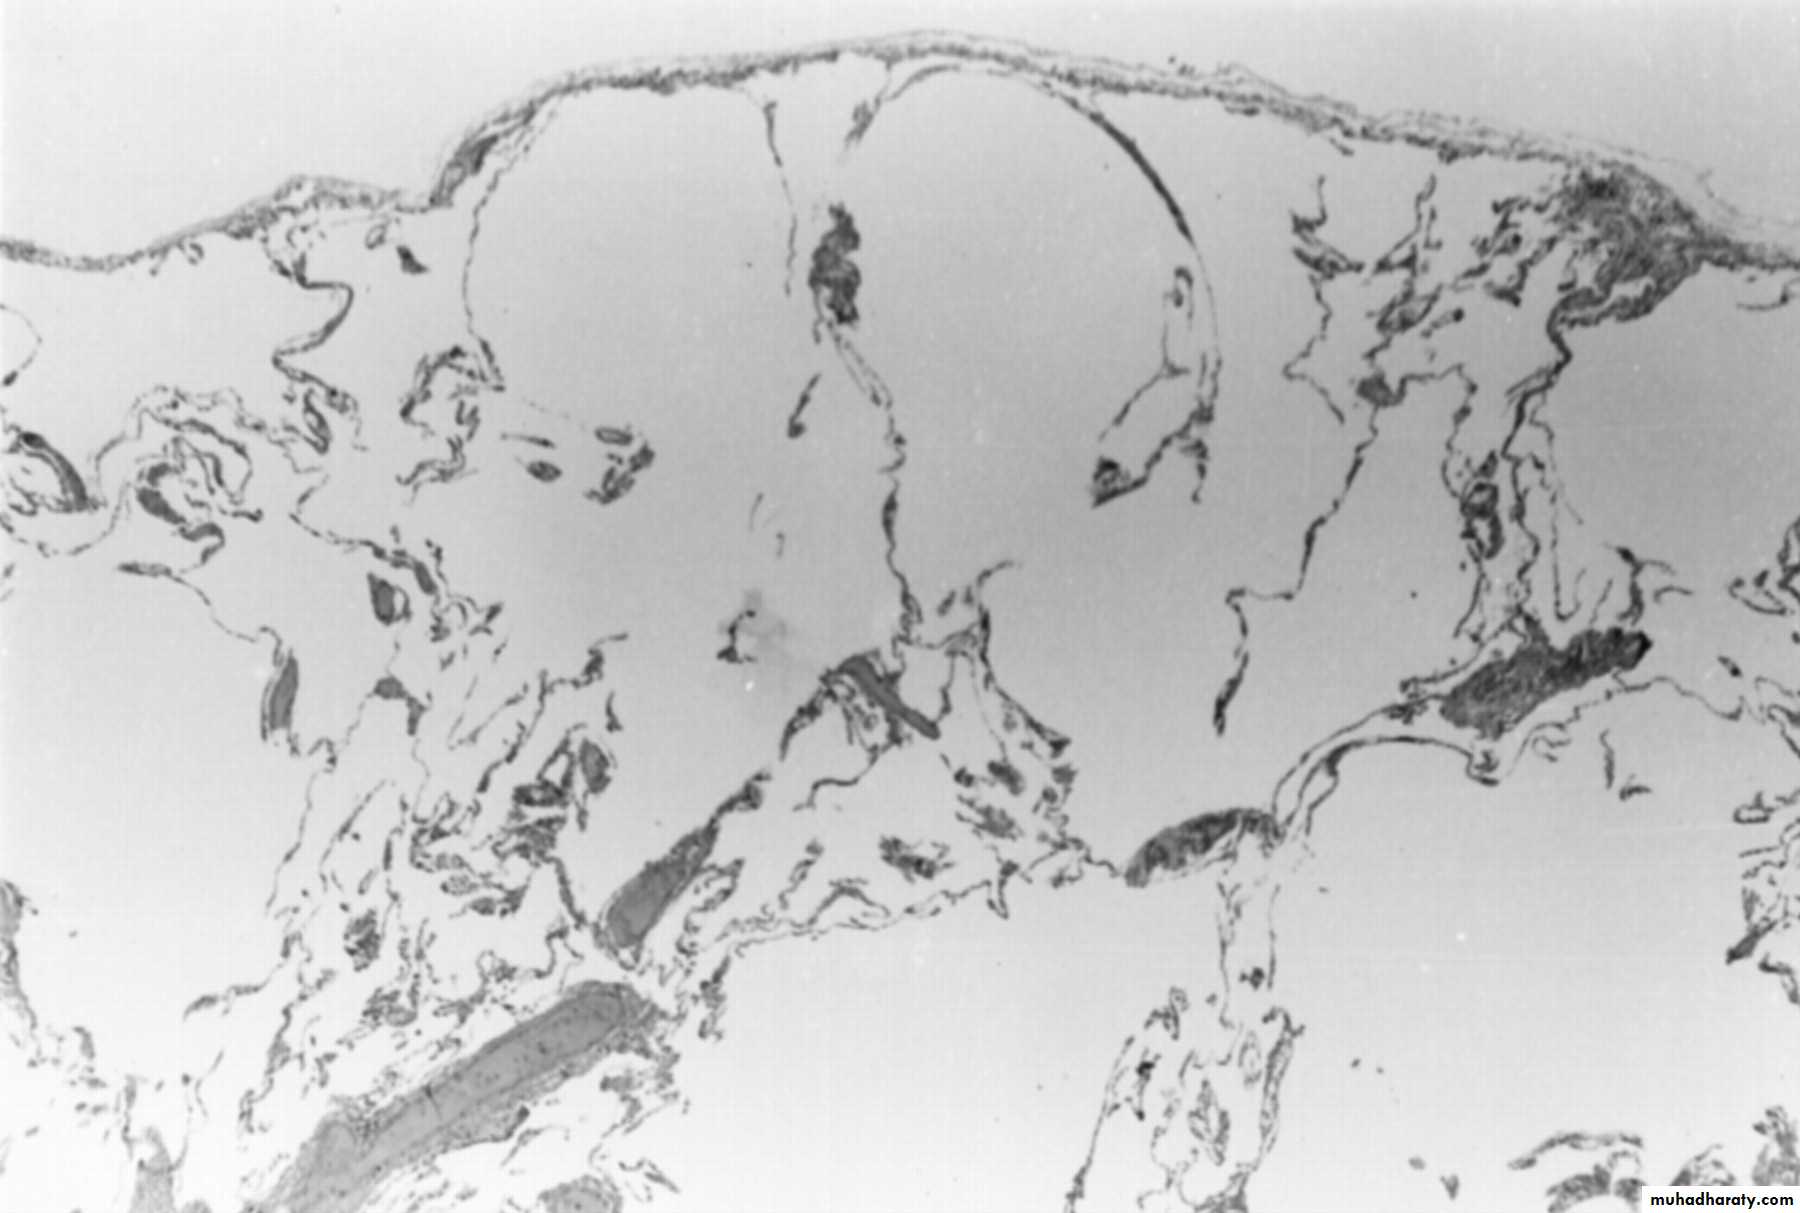

Liver Histology: A. Infiltration of a portal tract, by lymphocytes and a few eosinophils, and lymphocytic infiltration of the epithelium of a bile duct. B. Infiltration by lymphocytes in a portal tract, and the lobular parenchyma, with swelling of hepatocytes, and mild lobular disarray. C. A focus of Kupffer cell clustering, containing PAS-positive membrane debris and intrahepatic cholestasis (black arrow). D. Staining for collagen showing mild pericellular fibrosis.